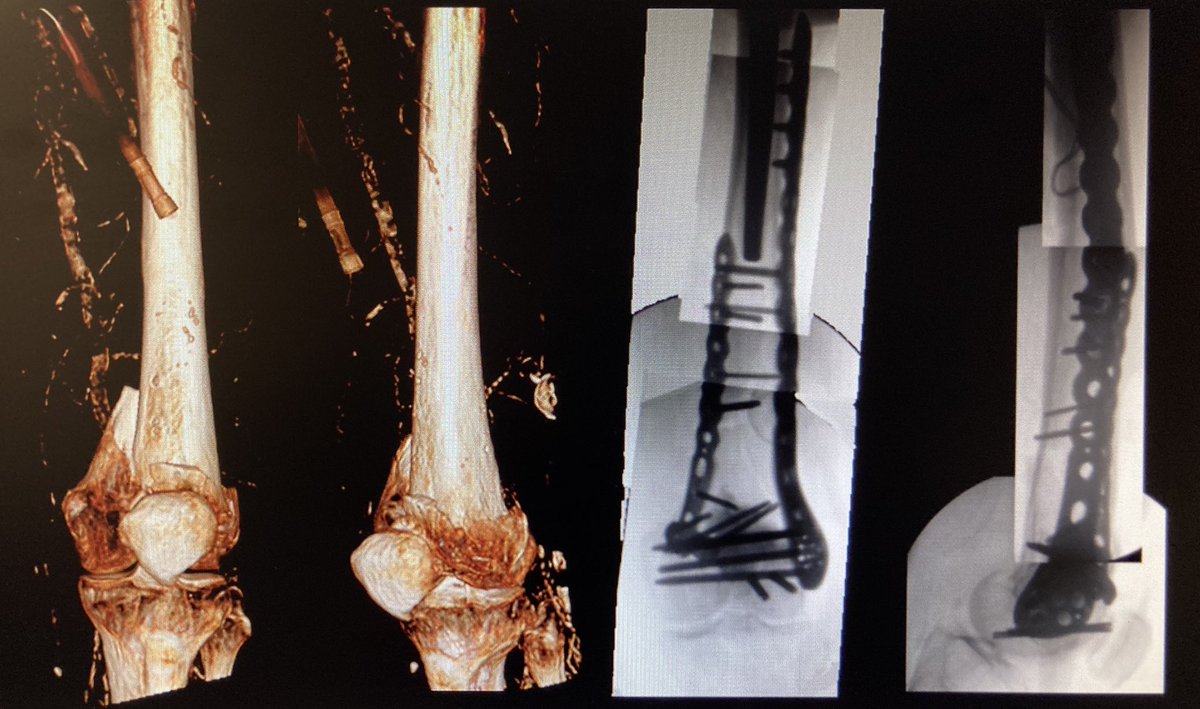

Interesting discussions recently in both clinical practice and emerging literature on these challenging fractures. Learning point for me: >40% intercondylar fractures have a Hoffa fragment. Bone & Joint 360 October 2020 edition ncbi.nlm.nih.gov/pmc/articles/P… #trauma #orthotwitter

Interesting discussions recently in both clinical practice and emerging literature on these challenging fractures. Learning point for me: &gt;40% intercondylar fractures have a Hoffa fragment. <a href="/BoneJoint360/">Bone & Joint 360</a> October 2020 edition ncbi.nlm.nih.gov/pmc/articles/P… #trauma #orthotwitter